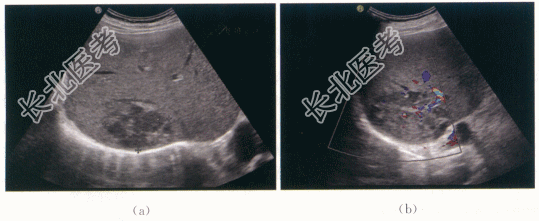

二、影像资料